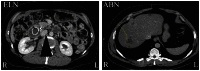

The present eye-movement study assessed the effect of expertise on eye-movement behaviour during image perception in the medical domain. To this end, radiologists, computed-tomography radiographers and psychology students were exposed to nine volumes of multi-slice, stack-view, axial computed-tomography images from the upper to the lower part of the abdomen with or without abnormality. The images were presented in succession at low, medium or high speed, while the participants had to detect enlarged lymph nodes or other visually more salient abnormalities. The radiologists outperformed both other groups in the detection of enlarged lymph nodes and their eye-movement behaviour also differed from the other groups. Their general strategy was to use saccades of shorter amplitude than the two other participant groups. In the presence of enlarged lymph nodes, they increased the number of fixations on the relevant areas and reverted to even shorter saccades. In volumes containing enlarged lymph nodes, radiologists' fixation durations were longer in comparison to their fixation durations in volumes without enlarged lymph nodes. More salient abnormalities were detected equally well by radiologists and radiographers, with both groups outperforming psychology students. However, to accomplish this, radiologists actually needed fewer fixations on the relevant areas than the radiographers. On the basis of these results, we argue that expert behaviour is manifested in distinct eye-movement patterns of proactivity, reactivity and suppression, depending on the nature of the task and the presence of abnormalities at any given moment.